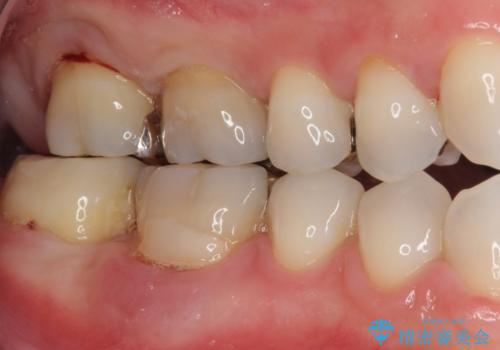

欠損と治療途中の奥歯 インプラント治療と補綴治療